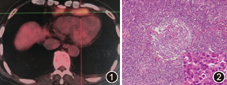

患者男,61岁,因"胸闷、气短5个月"于2012年8月1日以"多浆膜腔积液待查"入我院。患者入院前5个月受凉后出现发热,"抗感染治疗"后体温正常,但逐渐出现胸闷、气短,外院胸部CT检查见左肺舌叶片状影,前纵隔多发肿大淋巴结,心包少量积液;正电子发射计算机断层显像CT(PET/CT)示纵隔、胸骨旁及膈上前群多个淋巴结肿大(最高标准化摄取值为6.6,图1),双侧胸腔少量积液。多次检测胸腔积液中白细胞为(22~24.5)×106/L,单核细胞比例为0.84~0.96,胸腔积液与血清总蛋白比例为0.45~0.58,胸腔积液与血清乳酸脱氢酶(LDH)比例为0.43~0.89,胸腔积液LDH为80~151 U/L,提示介于渗和漏出液之间。胸腔积液病原学检查及病理检查无阳性发现。在当地医院行内科胸腔镜及胸膜活检均未见异常。因不除外结核,加用四联(异烟肼、利福平、乙胺丁醇和吡嗪酰胺)抗结核治疗3个月,随后给予泼尼松60 mg/d,2周后逐渐减量,但症状仍无缓解,故来我院。患者既往体健,每天饮白酒3~4两,40年;吸烟22.5包年,已戒烟4个月。体检:体温36.3 ℃,脉搏86次/min,呼吸21次/min,血压为120/80 mm Hg(1 mm Hg=0.133 kPa),未吸氧时脉搏血氧饱和度为96%,全身浅表淋巴结未及肿大,双下肺呼吸音降低,语颤减弱。双肺未闻及干湿性啰音。无杵状指,心脏及腹部检查未见异常。实验室检查:血、尿、便常规及血生化未见异常,24 h尿蛋白为0.19 g,甲状腺功能未见异常。ESR正常,超敏C反应蛋白为36 mg/L。血及胸腔积液的结核感染T细胞斑点试验检测均在正常范围。血清自身抗体和抗中性粒细胞胞质抗体均阴性。心脏彩色超声检查提示少量心包积液;肘静脉压为13 cm H2O(1 cm H2O=0.098 kPa)。CT肺动脉显像及静脉显像提示心包积液,双侧胸腔积液,心膈角区多发肿大淋巴结,未见肺栓塞征象。腹部B超示肝稍大;门静脉彩超示门静脉(主干内径为1.3 cm)流速偏低。多次复查胸腔积液仍介于渗出和漏出液之间,胸腔积液中腺苷酸脱氢酶、乳酸脱氢酶及淀粉酶均在正常范围。因诊断不明,在全身麻醉下行胸腔镜下心包前肿物切除术,术中发现肿物2块,1块位于右侧心膈脚附近与心包外脂肪融合生长,直径约为5 cm,触之质地较韧。另1块位于左侧心包外脂肪内,大小为4 cm×6 cm,与左侧心包外脂肪融合。切除组织的病原学检查阴性,病理回报:巨淋巴结增生(Castleman,浆细胞型,图2)。免疫组织化学染色CD138、CD38、浆细胞、CD20及CD31阳性,CD21及CD23部分阳性。